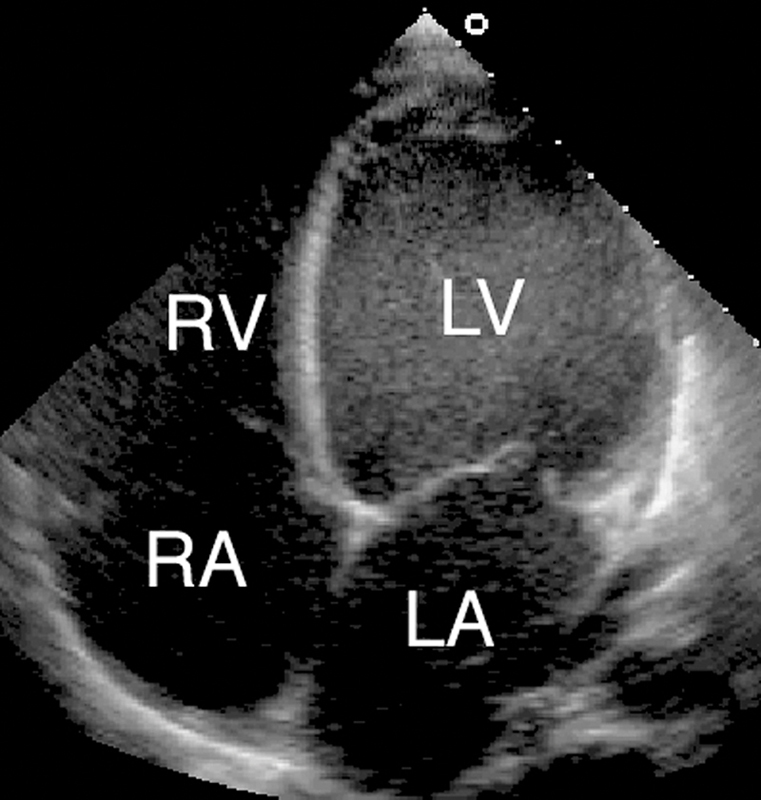

فحوصات تشخيصية لبعض امراض القلب والشرايين التاجية